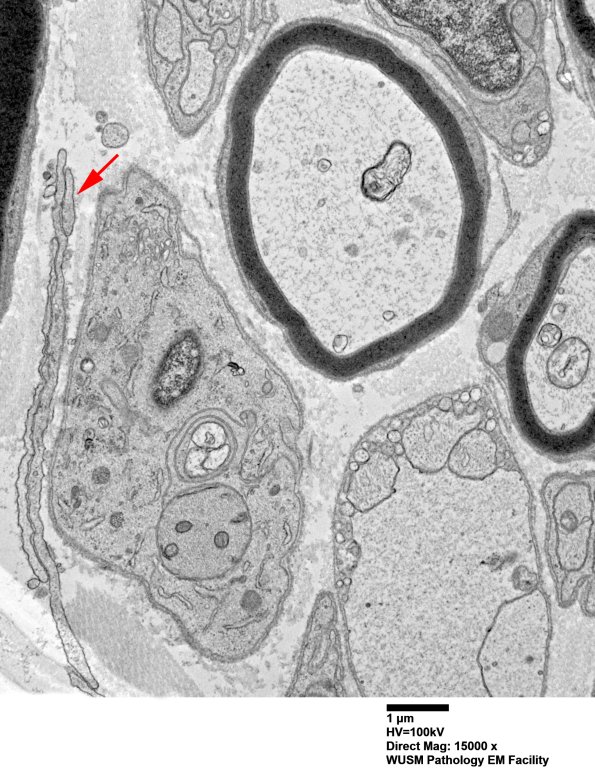

6B7-9 There are numerous processes and cells which are a bit difficult to place as perineurium or Schwann cell, lacking basal lamina but perhaps immature Schwann cells, or macrophages, lacking autophagosomes, although unchallenged histiocytic elements are still a possibility. We settled on the cells representing fibroblasts, running out of other actors. (electron micrographs)